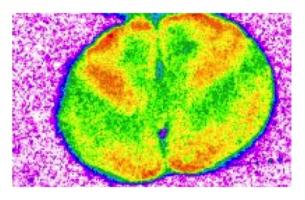

L'étude a suivi 3.869 participants, âgés de âgés de 30 à 50 ans à l'inclusion et à 73% des hommes. Les chercheurs ont pris en compte les données de consommation d'alcool sur 25 ans, mais aussi l'histoire du tabagisme, la pratique de l'exercice physique, le diabète de type 2. Les hommes étaient plus susceptibles d'être de gros buveurs par rapport aux femmes. Les chercheurs ont rapproché les données de consommation d'alcool avec les mesures de flux sanguin dans l'artère carotide-fémorale et les artères principales du cou et de la cuisse. Plus la vitesse du flux est élevée, plus l'est également la rigidité artérielle. L'analyse montre qu'une consommation régulière d'alcool, chez les hommes, au-delà des seuils recommandés est bien associée à une rigidité artérielle de nature à augmenter significativement le risque cardiovasculaire.